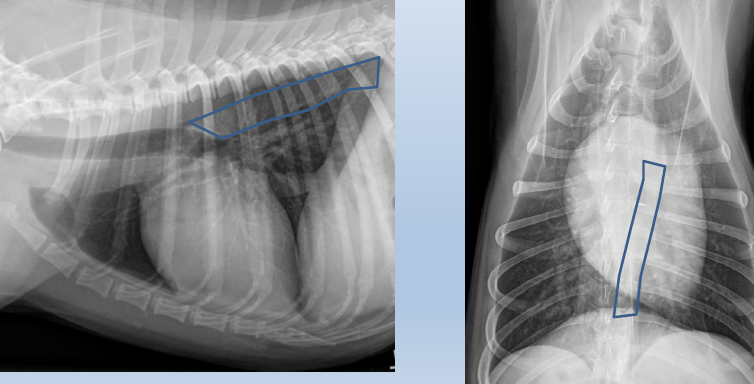

Lateral